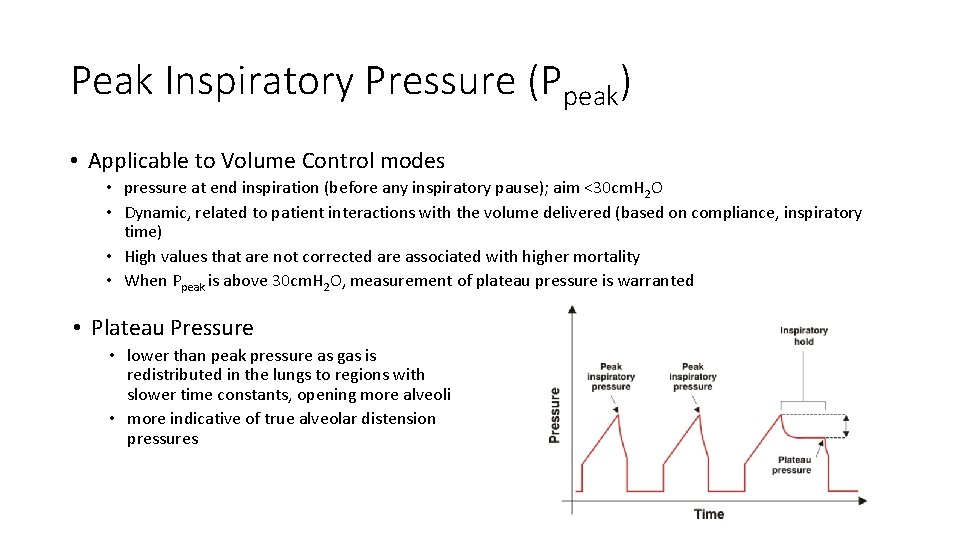

Peak Inspiratory Pressure (Ppeak) • Applicable to Volume Control modes • pressure at end inspiration (before any inspiratory pause); aim <30 cm. H 2 O • Dynamic, related to patient interactions with the volume delivered (based on compliance, inspiratory time) • High values that are not corrected are associated with higher mortality • When Ppeak is above 30 cm. H 2 O, measurement of plateau pressure is warranted • Plateau Pressure • lower than peak pressure as gas is redistributed in the lungs to regions with slower time constants, opening more alveoli • more indicative of true alveolar distension pressures